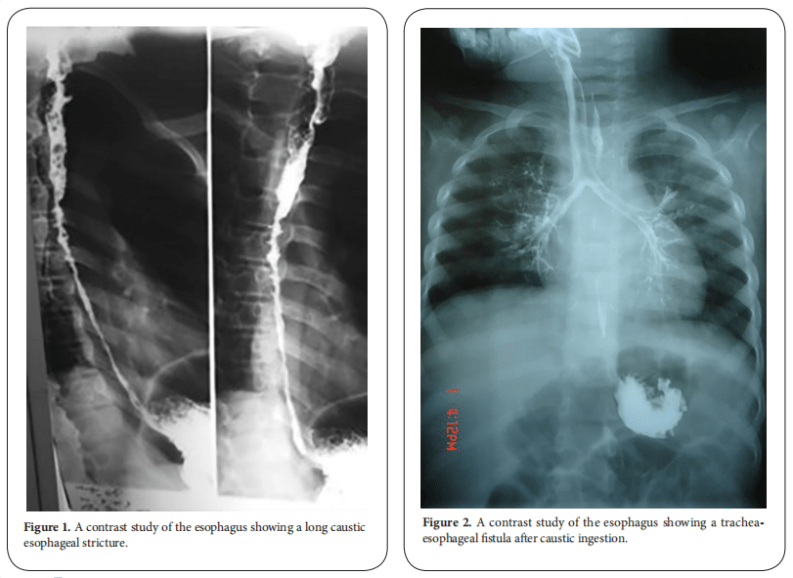

From www.antpublisher.com

Caustic esophageal stricture from diagnosis untill cure Abdelhay Clinical Surgery Research Chest Pain Esophageal Stricture Esophageal dysphagia refers to the sensation of food sticking or getting caught in the base of the throat or in the chest after. You may have difficulty swallowing food and liquids, and you may need. The esophagus is a tube that. An esophageal stricture occurs when your esophagus narrows, usually due to an illness or injury. The main symptom of. Chest Pain Esophageal Stricture.